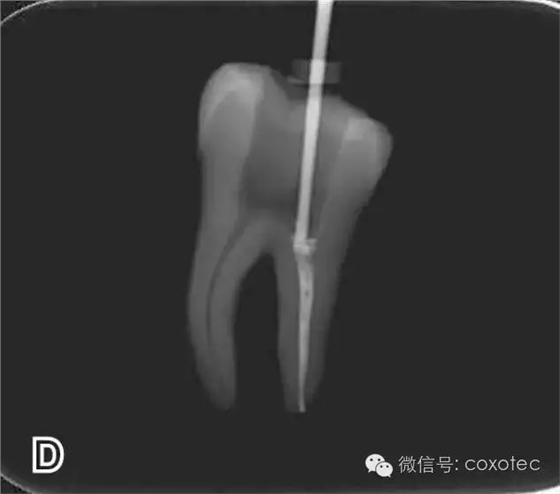

選擇的小號垂直加壓器應能自由到達距根尖4~5 mm(有學者提出3~4 Mm)的位置并能輕微接觸根管壁;中號垂直加壓器應能自由到達距根尖7~8 mm的位置并能輕微接觸根管壁;大號垂直加壓器應能自由到達距根尖10~11 mm的位置并能輕微接觸根管壁。用橡皮片做好標記(圖2)。

圖2 選擇垂直加壓器,A.試垂直加壓器 B.垂直加壓器在根內的位置 選擇非標準牙膠尖(如0.04、0.06 錐度牙膠尖)作為主尖,型號一般與根管預備最大號的器械型號一致,能到達距根尖0.5~1 mm 處,主尖尖段與根管壁緊密接觸。拍試尖X 線片進行確認(圖3)。